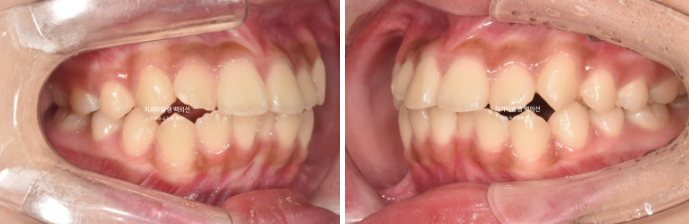

24.11

치료시작 1년 1개월차 모습입니다.

51번 장치를 끼고 있던 시기입니다.

발치공간은 1/3가량 남아있으며 덧니는 해소가 되었습니다.

배열은 많이 좋아졌지만 일부 장치가 안 맞는 부분이 있어 일찍이 재제작에 들어갔습니다.